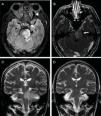

A 50-year-old male patient who, after 3 months of cranial brain trauma, presented proptosis, chemosis and exophthalmos in the left eye. Subsequently, dysmetria develops in the left extremities and right hemiparesis. The diagnosis of carotid-cavernous fistula (FCC) associated with hyperintensity of signal in FLAIR and diffuse contrast uptake at the level of the pseudo tumoral protuberance and cerebellar peduncle was established. This finding was compatible with venous congestion. His symptoms were fluctuating, he started with orbital symptoms and then from the posterior fossa with improvement of the orbital symptoms. FCC microcoil embolization produced resolution of ocular symptoms followed by improvement of brainstem symptoms. Magnetic resonance findings significantly reversed one year of follow-up. We describe a case of direct FCC with venous congestion in the brainstem and fluctuating symptoms with a considerable clinical and imaging improvement after treatment.